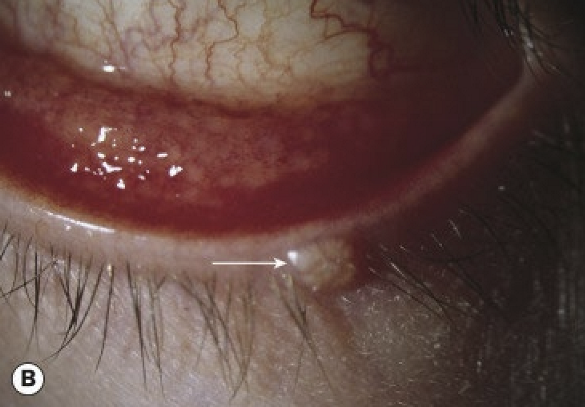

What conjunctival changes occur in cicatricial trachoma?

Conjunctival scarring

• Mild infection: linear or stellate scarring

• Severe infection: broad confluent scared (Arlt lines)

• Superior tarsal effected more then other areas of conjunctiva

<p>Conjunctival scarring </p><ul><li><p>Mild infection: linear or stellate scarring</p></li><li><p>Severe infection: broad confluent scared (Arlt lines)&nbsp;</p></li><li><p>Superior tarsal effected more then other areas of conjunctiva&nbsp;</p></li></ul><p></p>